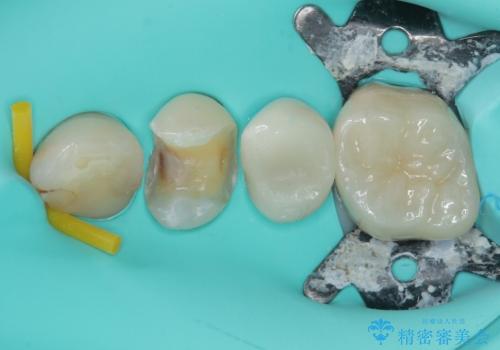

歯と歯茎の間に圧排糸と言われる糸を入れてシリコーン印象材にて精密な型どりをしました。

セラミックインレーの装着時には、唾液の侵入を防ぐために、ラバーダム防湿を行いました。